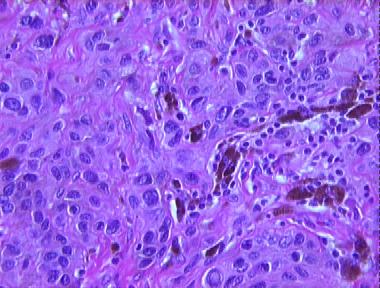

Histologic Features

- A large melanocytic lesion extending into the subcutis with

- A proliferation of banal melanocytic nests at the DE junction

- A proliferation of epthelioid "pagetoid-like" melanocytes as nests throughout the dermis

- Scattered dendritic melanocytes throughout the lesion

- A prominent number of melanophages laden with heavy melanin

- An admixture of smaller nevus cells at various foci

- A tendency for the cells and nests to surround rather than overrun the adnexae

- Little tendency for the nevus cells to mature with descent

- Absence of nuclear pleomorphism, mitoses, necrosis or ulceration

- A lymphocytic infiltrate at the base